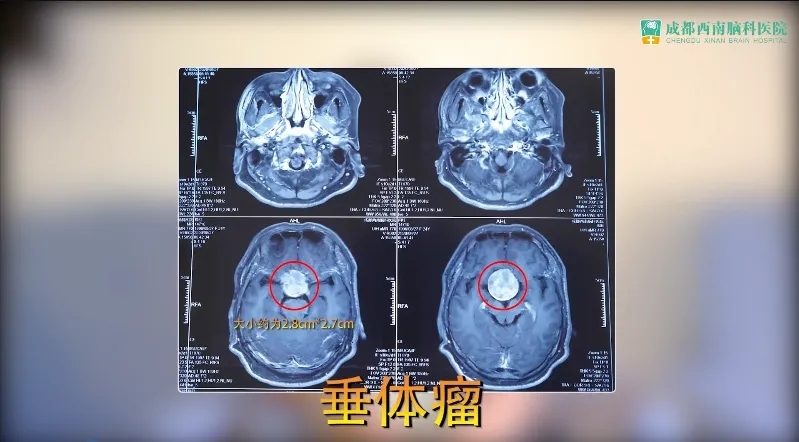

03 垂体瘤

垂体瘤是颅脑常见的肿瘤之一,多为良性,只有大约1%的可能会发展为癌。好发于青壮年,会影响生长发育、生育功能、学习、工作能力。除了直接压迫视神经引起视力下降以外,还可能引起激素的紊乱,面容变得粗犷,手足增大,身高显著高于同龄人,或者是脸庞变圆、变胖,心慌、燥热出汗多等。60%~90%患者可以通过手术完全切除肿瘤,大多数垂体瘤可以治愈。